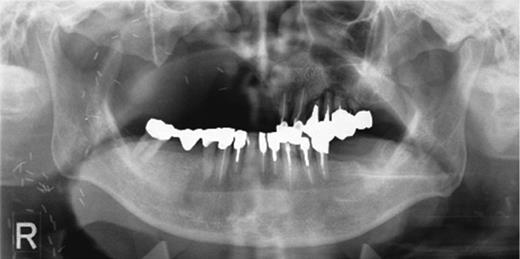

The bone mass in the left molar region was inadequate for implantation of fixtures.